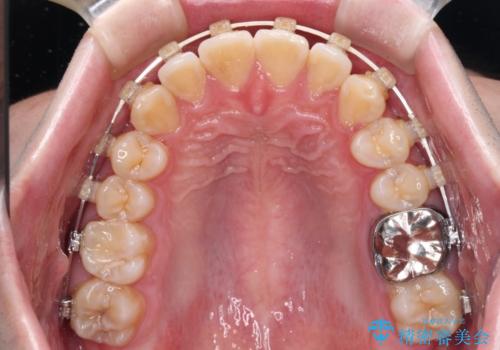

マウスピース矯正でもワイヤー矯正でも対応可能でしたが、インビザラインによる自己管理が煩わしいとのことで、ワイヤー装置にて矯正治療を行うこととしました。

下顎前歯が思っていた以上に動きが悪く、想定よりも期間がかかってしまいました。

矯正治療後には気になっていた銀歯をセラミックで自然な色に仕上げました。